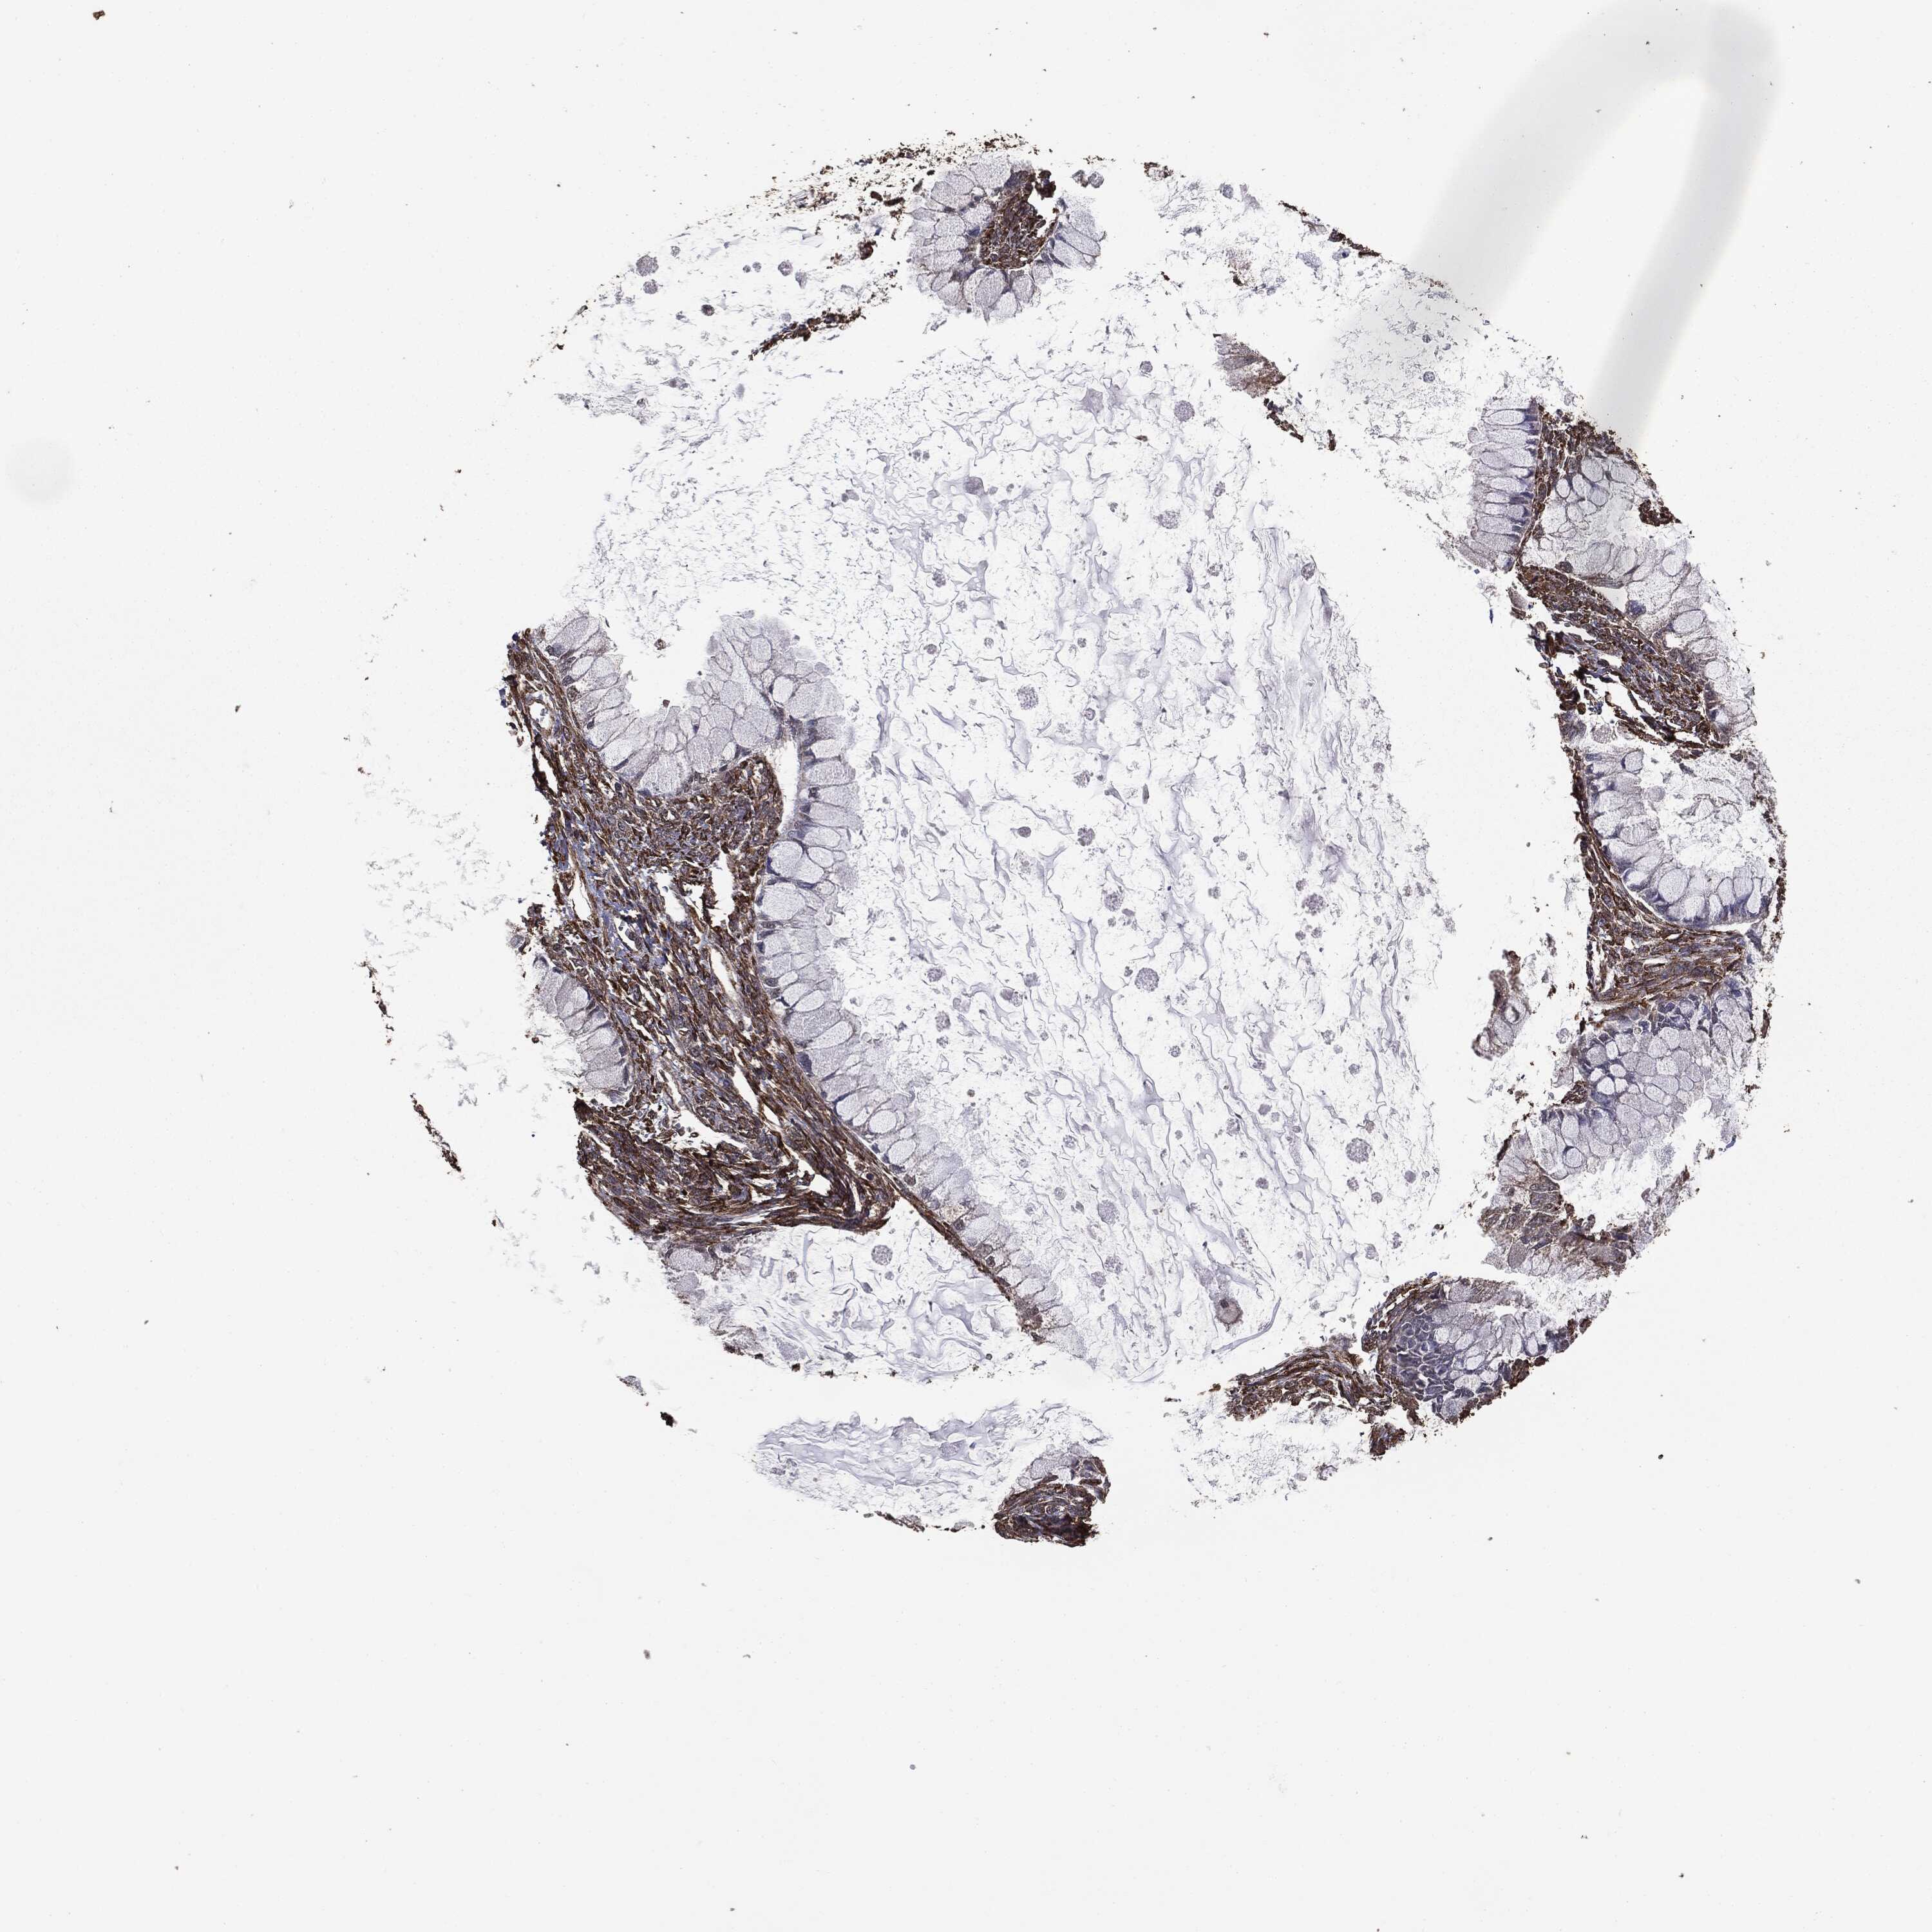

OVARIAN CANCER - Protein expressioni

A mouse-over function shows sample information and annotation data. Click on an image to view it in a full screen mode. Samples can be filtered based on level of antibody staining by selecting one or several of the following categories: high, medium, low and not detected. The assay and annotation is described here.

Note that samples used for immunohistochemistry by the Human Protein Atlas do not correspond to samples in the TCGA dataset.

Antibody stainingi

Antibody staining in the annotated cell types in the current human tissue is reported as not detected, low, medium, or high, based on conventional immunohistochemistry profiling in selected tissues. This score is based on the combination of the staining intensity and fraction of stained cells.

Each image is clickable and will lead to virtual microscopy that enables deeper exploration of all samples and also displays staining intensity scores, fraction scores and subcellular localization as well as patient and tissue information for each sample.

Cystadenocarcinoma, serous, NOS